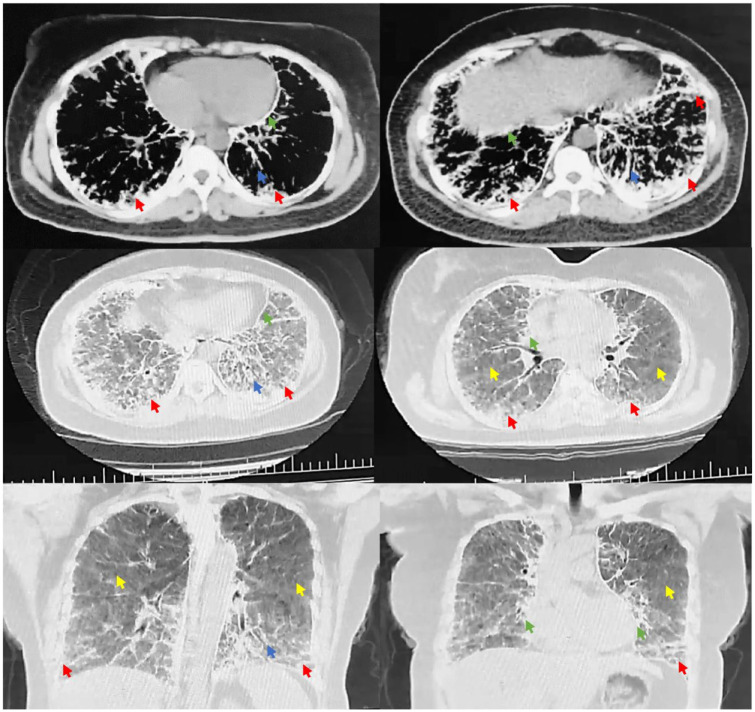

Pulmonary alveolar microlithiasis (PAM) is a rare genetic disorder that causes calcium phosphate microliths to form in the alveoli. Symptoms usually appear in a person's third or fourth decade of life. A definitive diagnosis does not always demand a lung biopsy but can be achieved in families with more than one member with PAM and compatible chest imaging. We present the case of a 47-year-old woman referred to us for shortness of breath. Chest imaging revealed bilateral diffuse ground-glass opacities, interlobar fissure calcification, and subpleural linear calcifications, leading to a diagnosis of PAM. Although there is no specific treatment for this condition, early diagnosis can help prevent it from progressing rapidly by avoiding exposure to risk factors.